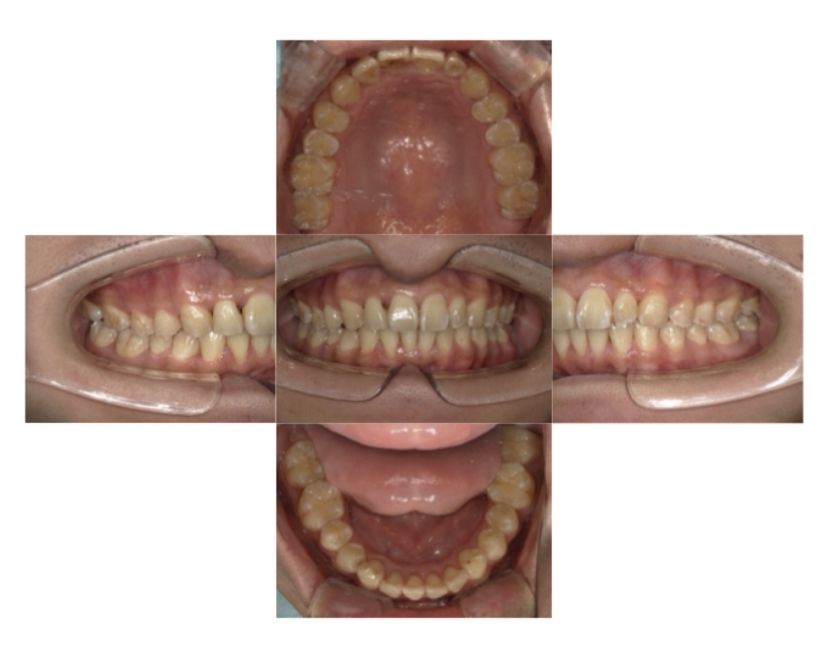

症例4

下顎前突、叢生

抜歯

ブラケット矯正

上下顎叢生、反対咬合(上下の前歯のガタガタ、若干受け口)のケースです。

装置はラビアル(上下表側)で、上下顎の小臼歯を4本抜歯を行っています。抜歯したスペースを使って、上下の叢生改善と前歯の受け口の改善を行っています。

主訴 前歯のガタガタを治したい。

年齢・性別 45歳 女性

お住まいの地域 神奈川県川崎市

治療方針 抜歯スペースを利用して上前歯の叢生(ガタガタ)の改善と受け口の改善

抜歯部位 上顎左右第一小臼歯、下顎左右第二小臼歯

使用装置 ラビアル(上下表側)、顎間ゴム

治療期間 2年6か月

治療回数 20回

リテーナー クリアリテーナー

BEFORE

AFTER